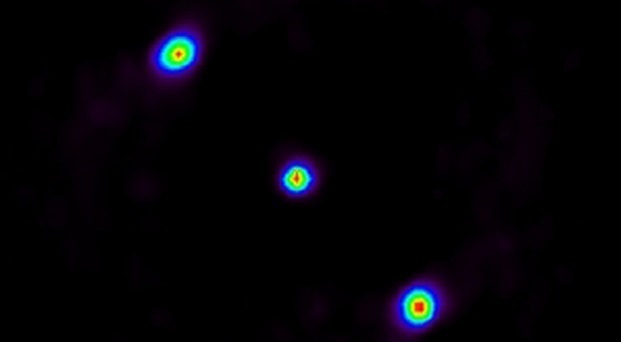

“Una alternativa és utilitzar la radiació gamma que produïx la interacció, més abundant i de producció més immediata”, explica Gabriela Llosá, investigadora del grup IRIS (Image Reconstruction, Instrumentation and Simulations for medical applications) a l’IFIC-IFIMED. S’està començant a fer proves en centres de teràpia hadrònica amb les anomenades ‘càmeres col·imades’, sistema que oferix una imatge simple, unidimensional, del que passa durant la hadronteràpia al cos del pacient. L’equip de l’IFIMED on treballa Llosá desenvolupa un sistema alternatiu: un telescopi Compton, una cambra formada per tres capes de bromur de lantà (LaBr3) que ‘centellegen’ al contacte amb les partícules gamma.

“Este sistema determina de manera més eficient on es diposita la radiació en la teràpia hadrònica”, sosté Llosá. L’avantatge d’este sistema davant de les càmeres col·imades és que aprofita millor la radiació gamma produïda en la interacció, pel que oferix més informació sobre la deposició de l’energia en el teixit. El principi de detecció és semblant al qual utilitzen els grans detectors que reconstruïxen el que passa en els xocs de partícules del Gran Col·lisiondor d’Hadrons (LHC) del CERN, on l’IFIC té àmplia experiència tant en la construcció com en l’operació de diversos dels seus experiments.

Tot i això, aplicar estos principis d’investigació bàsica a la clínica és complex: en primer lloc, “cal desenvolupar un dispositiu xicotet, que siga possible ubicar a la sala de hadronteràpia i alhora es realitza el tractament”, argumenta Llosá. Per a millorar l’eficàcia del dispositiu, relacionat amb la proposta que va rebre el Premi Idea el 2011, l’equip liderat per Gabriela Llosá i Josep Oliver ha inclòs una tercera capa en la càmera, les primeres imatges de la qual es van publicar en la revista ‘Frontiers in Oncology’.